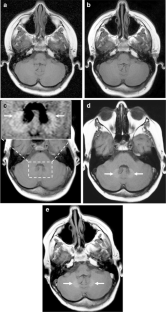

Fig. 1

Fig. 2

Fig. 3

Fig. 4

Fig. 5